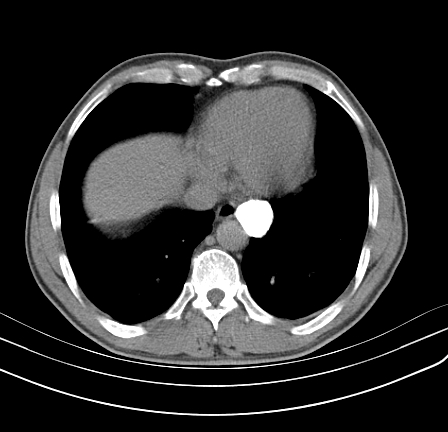

以下是引用影像孺子牛在2009-5-20 23:18:00的发言:[br]左侧后心膈角处类椭圆形钙化灶,最常见的是淋巴结钙化,但太大了不支持,其它如食管囊肿钙化、实性畸胆瘤等。何东西钙化真不好定。

以下是引用zbp537在2009-5-20 20:52:00的发言:[br]钙化灶,来源不好说。